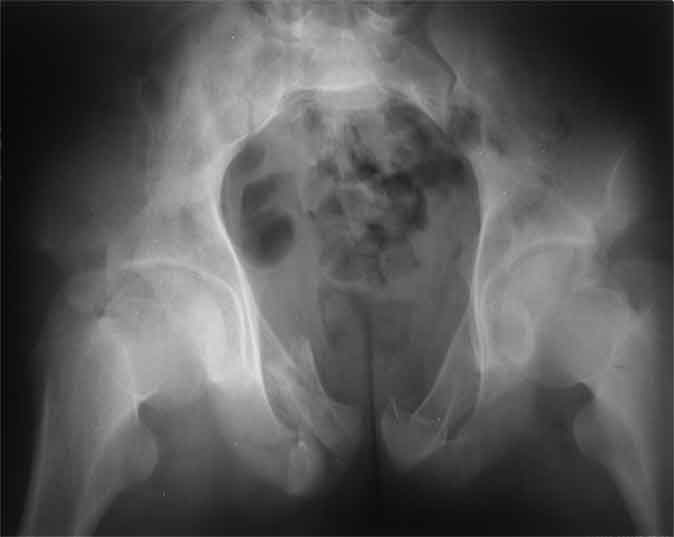

Не смог разглядеть на представленных картинках частичное повреждение левого КП, повреждение Денис1-2 справа? 3Д реконструкции в инлет и боковой проекциях убедительно не демонстрируют типа повреждения задних отделов тазового кольца(справа боковая масса скомпремирована), Наверное, у тебя есть возможность оценить тип перелома крестца по прямой проекции 3Д.

По вертлуге- смог разглядеть только изолированный перелом передней колонны.

Насколько я понял из твоего письма, обращенного к анонимному vit, ты не видишь показаний к реконструкции перелома. Я бы взялся за реконструкцию(илео-ингвинальный доступ), хоть прошел и месяц после травмы: боковая 3Д показывает смещение нагрузочной зоны впадины, что однозначно будет способствовать разрушению хряща головки и впадины( особенно у 16 летнего пациента с ожидаемым высоким уровнем активности) + изменение геометрии впадины за счет неустраненного смещения фрагментов колонны (КТ, 3Д данные).

На мой взгляд, без реконструкции этот сустав обречен (концепция вторичной конгруэтности в данных условиях работать не будет), реконструкция дает шанс на восстановление функции сустава.

По представленным материалам, мне кажется, перелом был передней колонны ацетабулум с минимальным вовлечением нагрузочной поверхности сустава, левосторенний повреждение КПС и лонных костей.

При свежем случае показана фиксация передней колонны к задней (снимки), компрессирующим винтом минимальным перкутанным методом по супраацетабулярной линии и в зависимости от состояния КПС.

Стандартные снимки ацетабулума по Judet и снимки таза (инлет и оутлет) подскажут дальнейшую тактику по нагрузке.